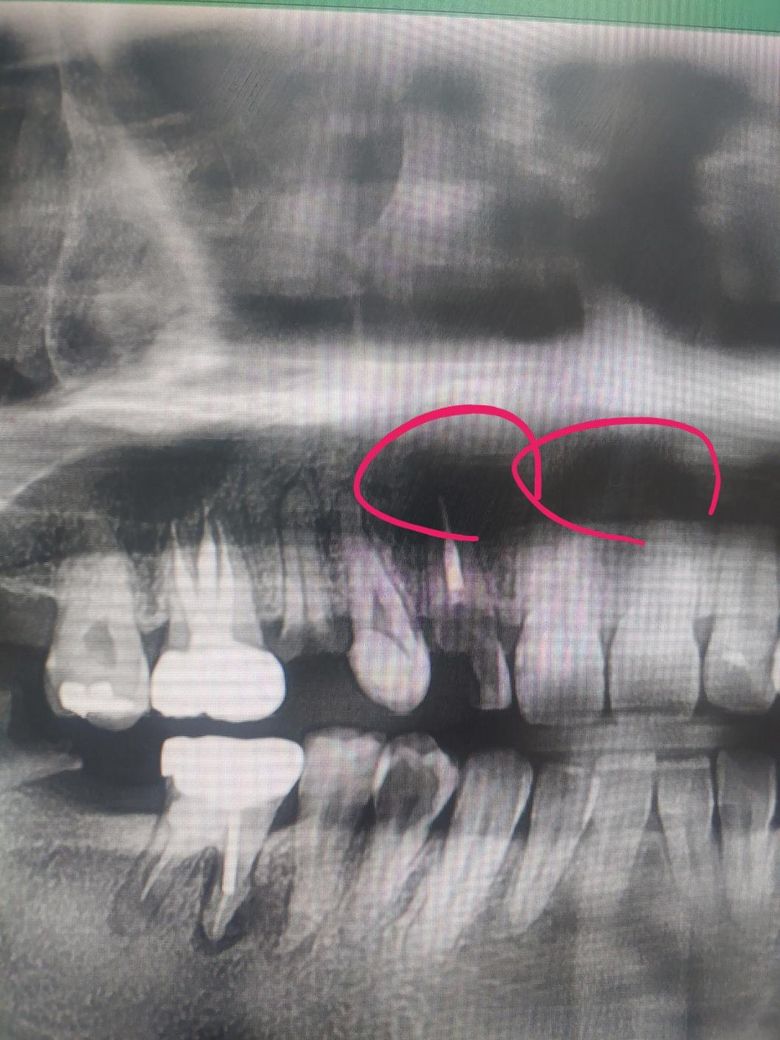

치아 파노라마 상에 앞니들 위에가 검게 보이는데 잇몸 뼈랑 뿌리가 염증때매 녹은걸까요?

치아 파노라마 상에 앞니들 위에가 검게 보이는데 잇몸 뼈랑 뿌리가 염증때매 녹은걸까요..................?

• 2번 째 사진

위쪽에 나타나는 검은 색 부분은 충치나 염증에 의해서가 아닌 조직의 밀도에 의한 차이로 인한것입니다.

저부위는 잇몸뼈가 녹은게 아니라 연조직과 겹쳐서 보이는곳 또는 콧구멍등이 겹쳐서 그렇게 보이는겁니다.

잇몸 뼈와 치근의 염증으로 인한 녹음(흡수)일 가능성도 있습니다. 치아 뿌리 주변에 염증이 생기면, 그 부위의 뼈가 흡수되어 검게 나타나게 됩니다.

보다 정확한 상태 확인읠 위해 치과에 방문하여 실제로 상태를 보면서 확인이 필요로 됩니다.